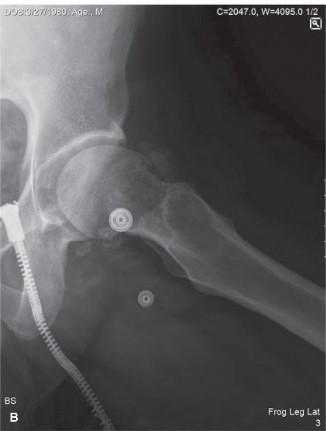

A 45-year-old male presents to your office with right hip pain. The pain worsens with activity and started indolently about 2 years ago, without a preceding traumatic event. He also reports clicking and catching of the hip joint. He is worried that he has osteoarthritis and is anxious about getting a hip replacement at such a young age. X-rays are shown in Figure 8–32A and B.

Figure 8–32 A–B

The correct answer is (D). Synovial chondromatosis is a metaplastic proliferation of hyaline cartilage nodules in the synovial membrane. It causes pain and mechanical symptoms such as clicking, popping, and stiffness. It is most common in the hip and knee but has been reported in other joints. Initially the cartilage nodules are not visible on plain radiographs, and MR is required to visualize them. However, over time, the nodules calcify and become radiopaque. Erosions and joint destruction can occur over time.